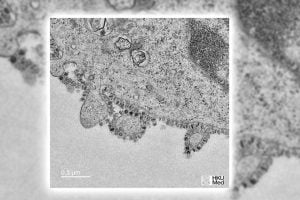

نشرت جامعة “هونغ كونغ” الصينية الليلة، الصورة الأولى لـ”فيروس كورونا” الناشئ في مدينة “ووهان” وسط الصين.

ووفقًا لما أوردته صحيفة ” ذي إندبندنت تركيا” وما ترجمته “تركيا الآن” فإن الصورة ملتقطة من مصاب يحمل الجنسية الصينية وبواسطة مجهر إلكتروني.

ويقول الأستاذ في جامعة “هونغ كونغ” جون نيكولز إن: “كل خلية مصابة في جسم الإنسان مُصابة بـ”فيروس كورونا” تنتج الآلاف، ويمكن أن تؤثر هذه أيضا على الخلايا الجديدة”.

وتختلف الدراسات حول كيفية انتشار الفيروس خلال هذه الفترة الزمنية القصيرة، لكنها أكدت أن معدل تكاثره مشابه إلى حد كبير لتكاثر “الخلايا السرطانية”، وفقًا للأستاذ الجامعي.